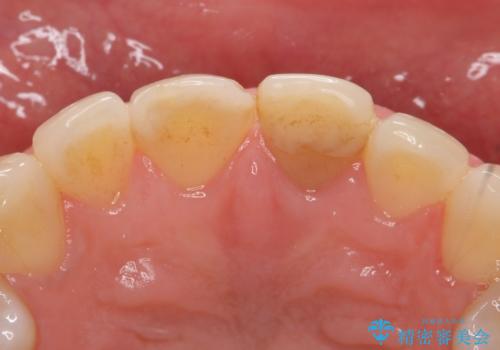

オールセラミッククラウン 変色が気になる前歯の治療

- 前歯の変色が気になるのでセラミックによる治療を行いたいといらっしゃった方の症例です。

左上1番目の歯の再根管治療終了後、左右1番目の2歯をオールセラミッククラウンで補綴しました。